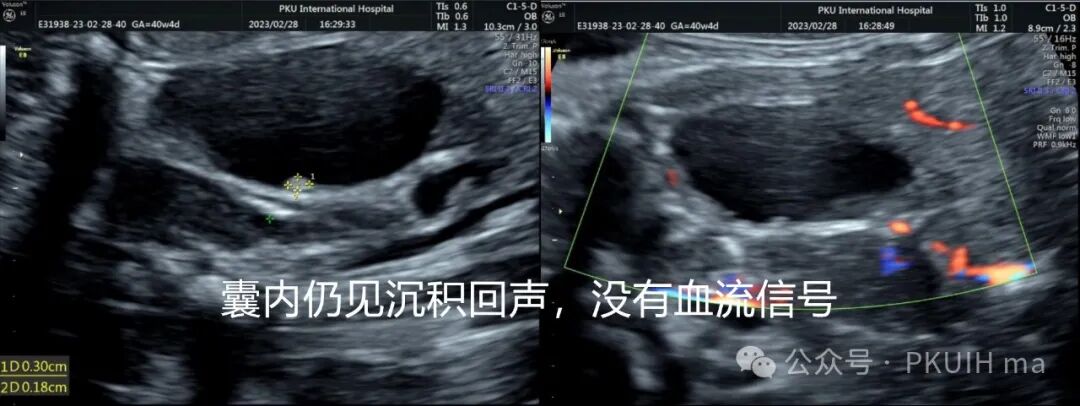

在随后的随访观察中(如下图)发现囊肿大小和内部回声有变化。最终考虑是卵巢出血性囊肿(卵巢扭转待除外)